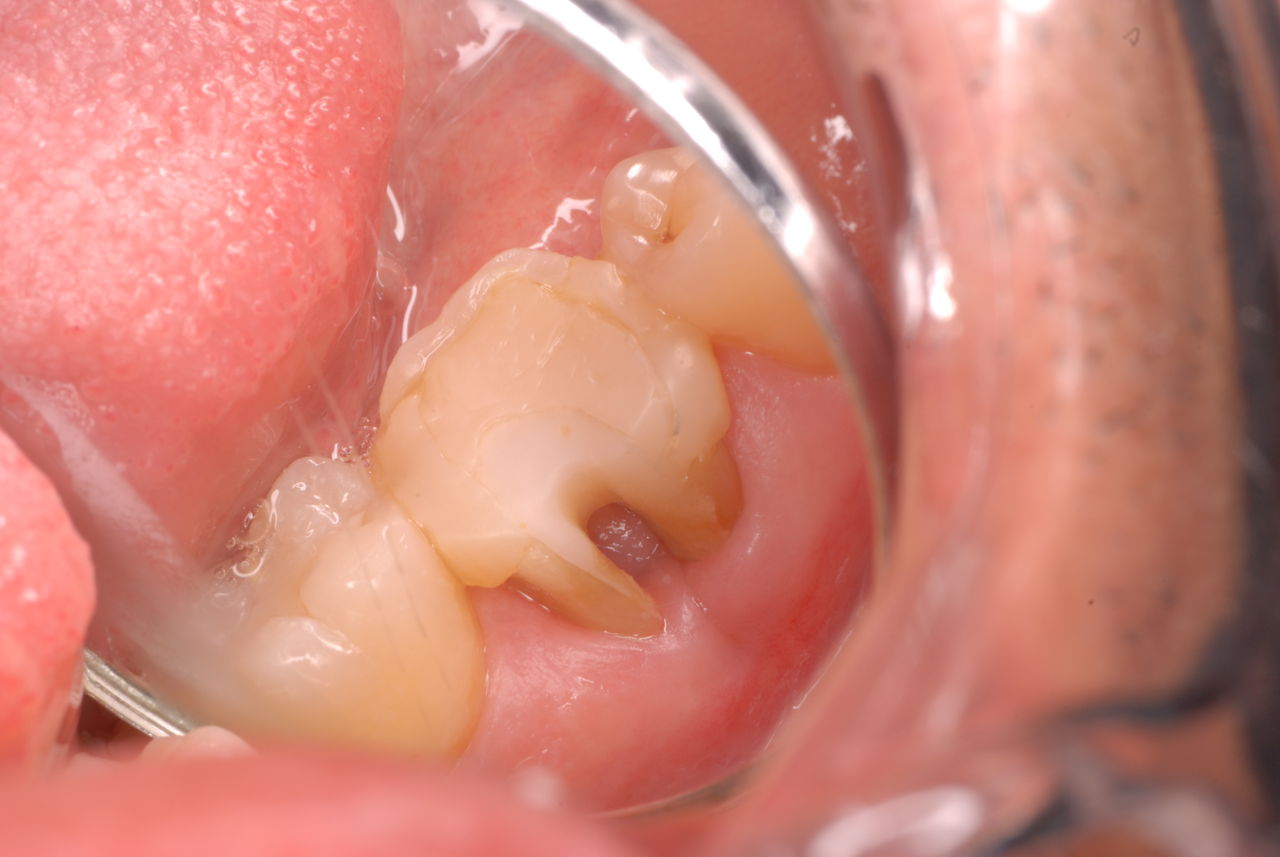

他の都心の矯正歯科で治療中で、ほぼ終了近くの方でした。歯並びで言えば上下の歯が突出していて唇が閉じにくいというのをなんとかしたい。そして歯を抜かないで出来るところを探して都心の矯正歯科への通院となりました。ところが本人曰くよく噛めないというのです。

相談しても“問題無い”の説明だけだそうです。調べたところ歯周病は進行しているし、奥歯の大きい歯2本ずつ計4本はしっかり噛んでいないのです。よく噛めないというのはそのことのようでした。これを矯正的に元に戻すことはできない訳ではありませんが、時間と手間がかかるのは間違いないことです。

歯を削らないといいましても結局歯の間を削りスペースを確保したそうですから、何らかの歯に対する傷害はしているのです。それは虫歯や歯周病を起こしやすい理由にもなりますからこれからも要注意なのです。二年間という貴重な時間を費やしていますから患者本人は大変だったと思います。そして二年間を要したならば更に二年間動かないようにするための入れ歯やマウスピースを装着し続けなければいけないのです。